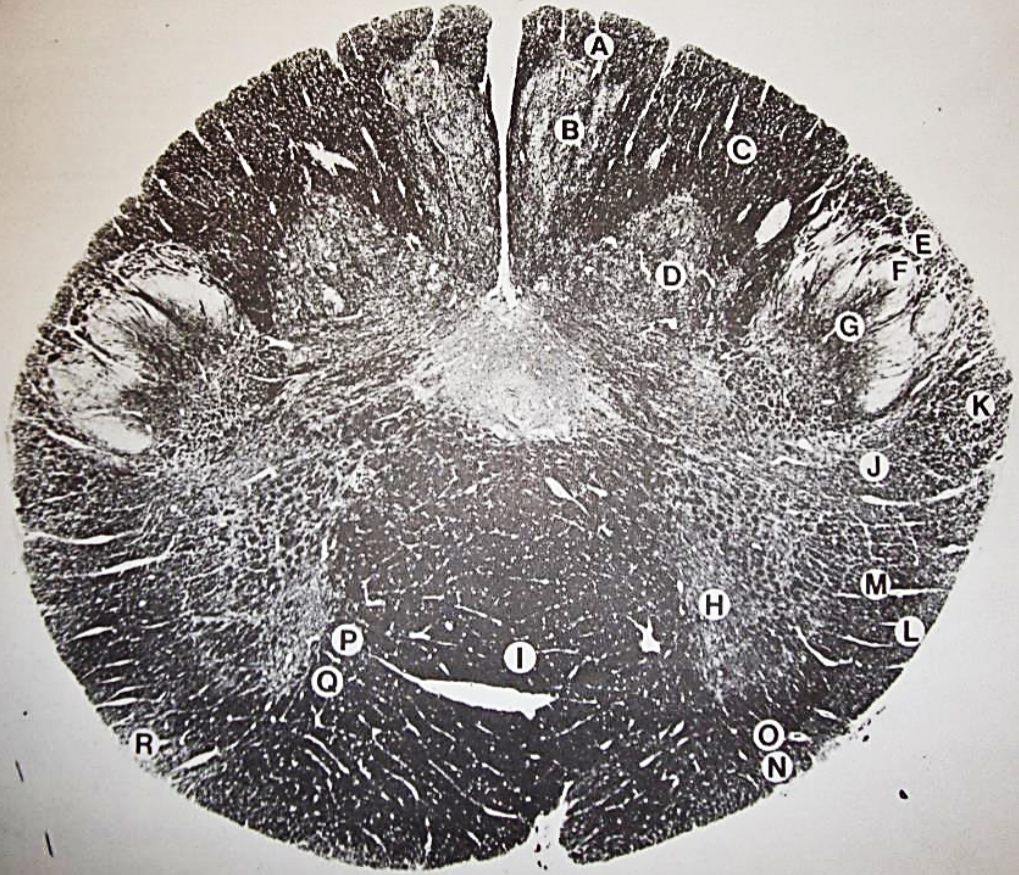

A

posterior median sulcus

B

posterior intermediate sulcus

C

anterior median fissure

D

gracile fasciculus

E

Gracile nucleus

F

fasciculus cuneatus

G

spinal trigeminal tract

H+I collectively

spinal trigeminal nucleus

J

Accessory nucleus

K

pyramidal decussation

L

lateral corticospinal tract

M

rubrospinal tract

N

posterior spinocerebellar tract

O

anterior spinocerebellar tract

P

lateral spinothalamic tract

Q

anterior spinothalamic tract

R

lateral vestibulospinal tract

S

medial longitudinal fasciculus

T

tectospinal tract

U

central canal